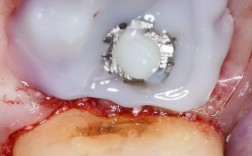

基台连接与取模:

- 骨结合完成后,医生会进行二期手术(有时是微创方式),暴露种植体顶部,连接基台(连接种植体和牙冠的中间部件)。

- 然后取模,制作最终的牙冠(通常为全瓷冠)。

戴牙冠:

(图片来源网络,侵删)- 牙冠制作完成后(通常需要1-2周),医生会将其固定在基台上。

- 调整咬合,确保舒适、功能正常、美观自然。